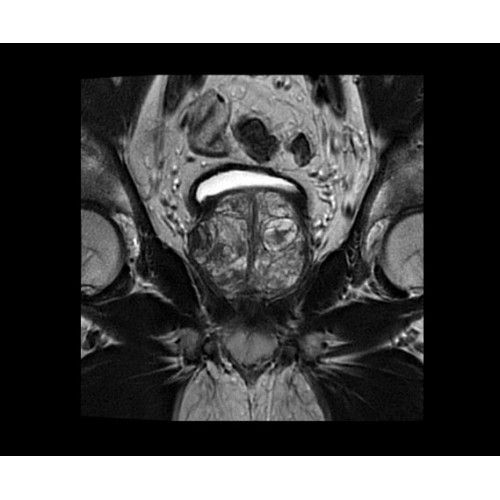

SIGNA PET/MR 3.0T — это гибридная система, в которой совмещаются две принципиально разные технологии — магнитно-резонансную томографию (МРТ) и позитронно-эмиссионную томографию (ПЭТ). Система отличающийся высокой чувствительностью и эффективностью и предназначена для диагностики в области онкологии, неврологии, кардио-васкулярных исследований, исследований воспалительных процессов.

• TurboTOF — инновационная технология позволяет корректировать коэффициент затухания сигнала и минимизировать потери анатомических данных, создавая МР-систему для количественной визуализации.

• МРТ с функцией нулевого времени эхо (ZTE) отличается точностью, возможностью персональных настроек и отсутствием ионизирующего излучения. Она приходит на смену традиционному исследованию на основе рентгеновского излучения. МРТ с функцией нулевого времени эхо (ZTE) на базе SIGNA ПЭТ/МРТ является более надежной и быстрой по сравнению с системами, использующими сверхмалое время эхо (UTE).